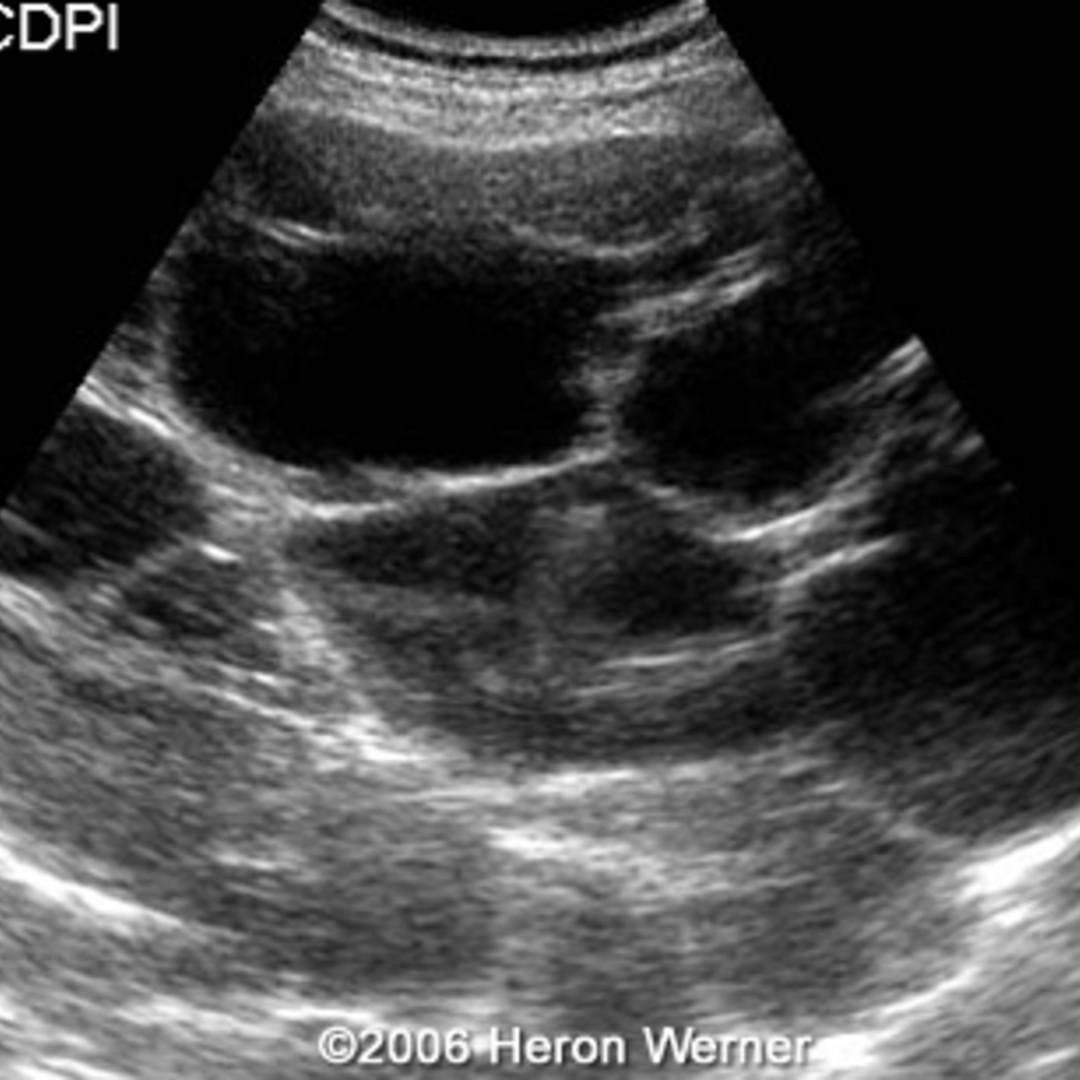

📃 Multicystic liver disease and pregnancy

The fetal liver in the second trimester. A portal area and part of the Chicken Liver During Pregnancy Second Trimester Pregnancy is a wonderful phase in a woman’s life, accompanied by a series of uncertainties and questions regarding what she. A pregnant woman who eats liver regularly may consume enough vitamin a to. Is it safe to eat chicken liver during second trimester of pregnancy? Liver contains high levels of retinol. No, it's not safe to eat liver during pregnancy. Chicken Liver During Pregnancy Second Trimester.